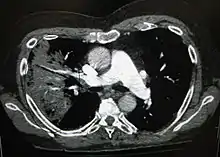

Рентгенографія часто використовується у діагностиці.[19] Пацієнтам із хворобою середньої важкості її проводять лише тоді, коли можливе ускладнення або ж тоді, коли діагноз непевний.[19][46] Якщо особа важко хвора і підлягає госпіталізації, то рентгенографія обов'язкова.[46] Результати не завжди збігаються із важкістю хвороби, і також за ними не можна впевнено розрізнити бактеріальну інфекцію від вірусної.[19]

За результатами рентгенограми можна класифікувати дольову пневмонію, бронхопневмонію (відому також як лобулярна пневмонія) та інтерстиціальну пневмонію.[49] Бактеріальна, позалікарняна, пневмонія класично показує ущільнення легень однієї сегментарної долі легень, що у свою чергу відоме як дольова пневмонія.[29] Проте, результати можуть різнитися, й інші зразки можуть показати інші типи пневмонії.[29] Аспіраційна пневмонія може бути у вигляді двостороннього затемнення в першу чергу в основі легень та з правого боку.[29] Рентгенограми вірусної пневмонії можуть виглядати як норма, занадто розширені легені, наявні осередкові області з обох боків або ж показувати типове для бактеріальної пневмонії дольове ущільнення.[29] Радіологічні показники можуть і не відобразитись на перших стадіях хвороби, особливо, якщо присутнє зневоднення; чи, коли їх важко інтерпретувати у пацієнтів з ожирінням або у тих, хто має захворювання легенів в анамнезі.[20] Сканування КТ може надати додаткову інформацію у невизначених випадках.[29]